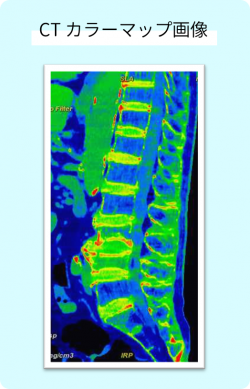

>Dual Energy CT(デュアルエナジーCT)

2種類のエネルギーのX線で撮影するCTです。通常のCTでは分かりにくい物質の性質や成分の違いを見分けることができます。

たとえば、

- MRIでしか分からなかった腰の圧迫骨折などの判定

- 尿路結石の成分の推定

など、診断の精度向上に役立っています。